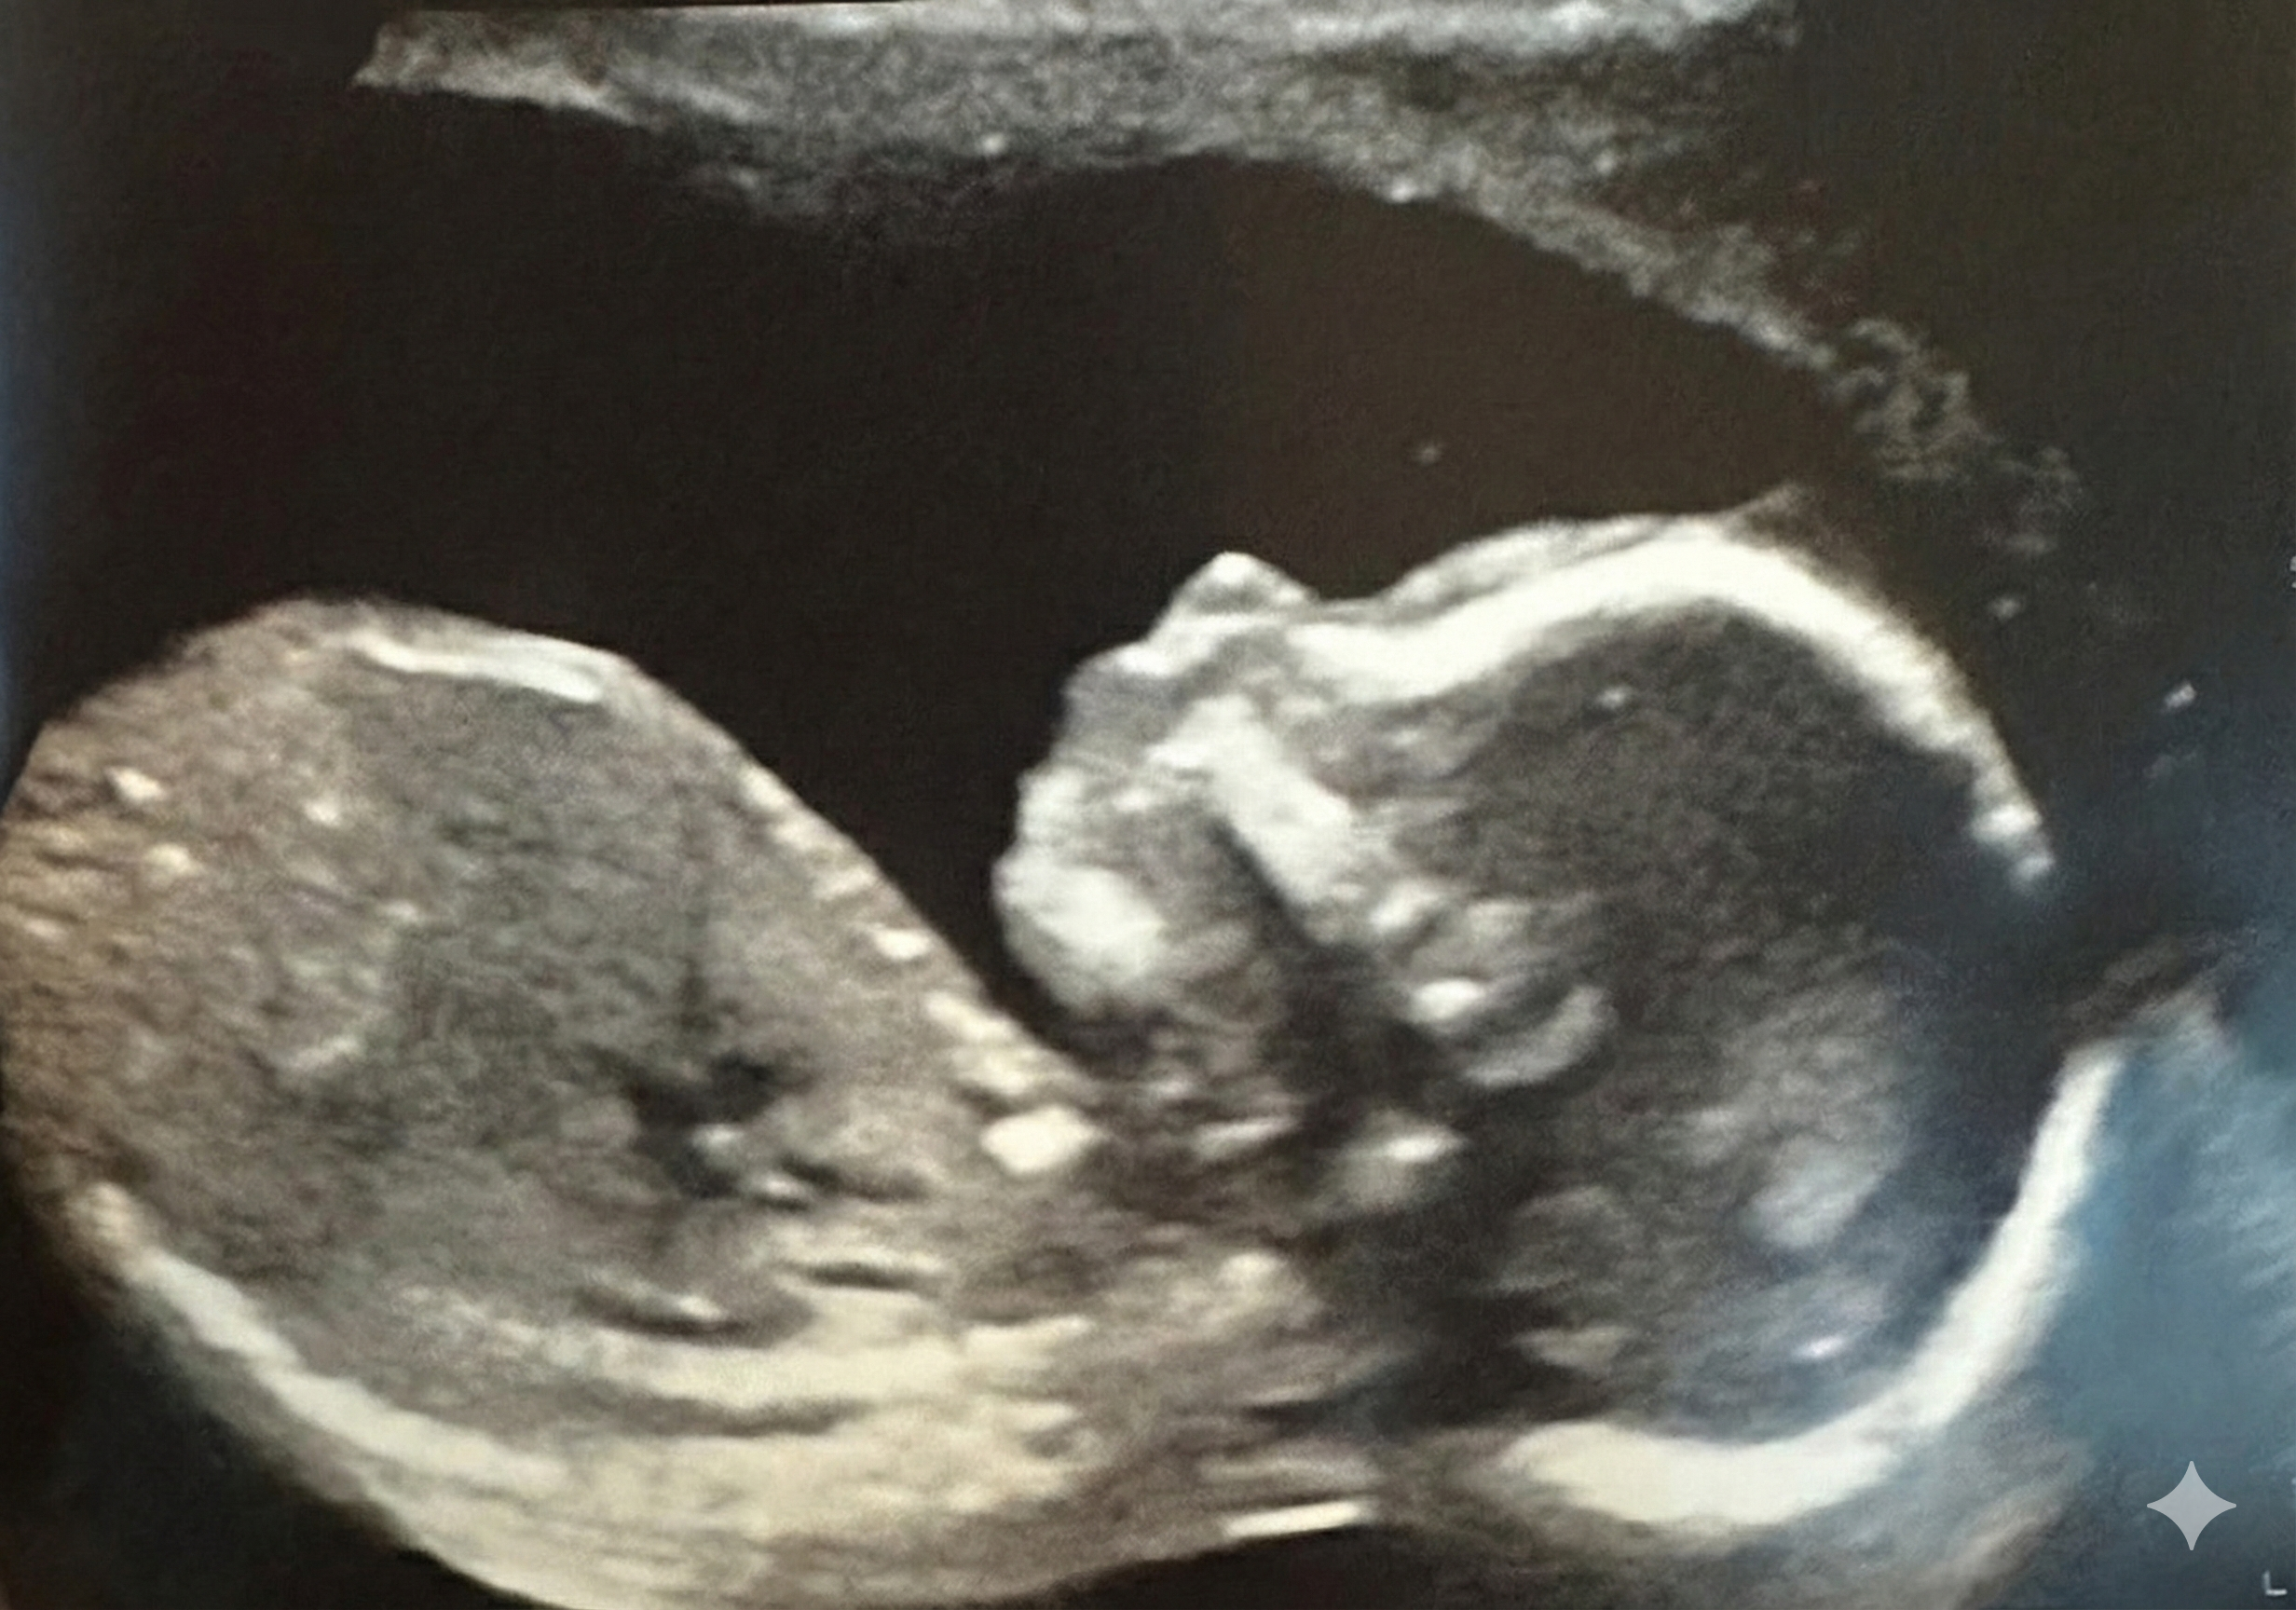

CelebratingBaby Zoe

Our Sweet Zoe Rose Is in Bloom

Join Tracy and Dorian as they celebrate the upcoming arrival of their baby girl. Your presence would make this day even more special.